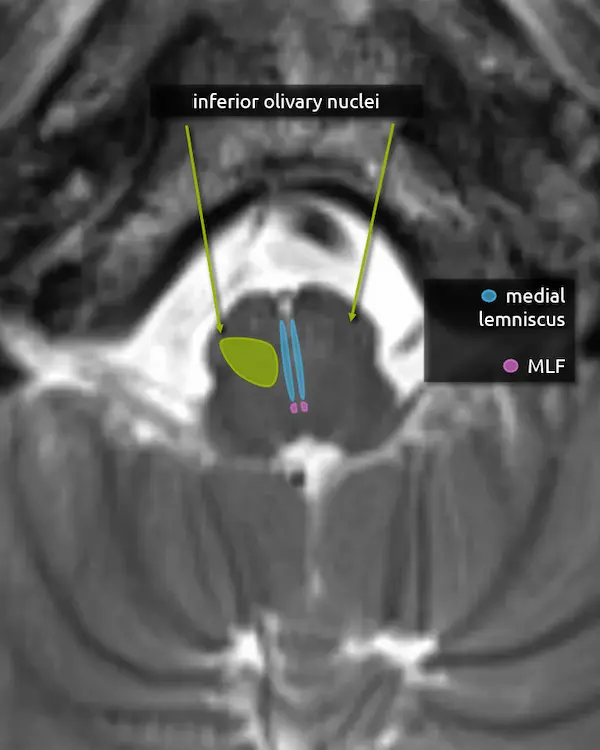

1. Pyramids

2. Inferior cerebellar peduncles

3. Medial lemniscus

4. Medial longitudinal fasciculus (MLF)

5. Inferior olivary nucleus

The inferior olivary nucleus is located in the upper medulla just posterior to the pyramids. It is involved in motor coordination and is a main component of the dentatorubro-olivary pathway (aka the triangle of Guillain and Mollaret), discussed below. A lesion that damages the predominantly inhibitory interneurons in the tracts connecting the corners of the triangle may result in disinhibition of the inferior olivary nucleus, characteristically but rarely manifesting as palatal myoclonus. Over time, the inferior olivary nucleus may swell, become T2 hyperintense, and eventually atrophy, a process called hypertrophic olivary degeneration.

Dentatorubro-Olivary Pathway

(Triangle of Guillain-Mollaret)

The dentatorubro-olivary pathway (aka the triangle of Guillain and Mollaret) forms a triangle with corners at the red nucleus in the midbrain, the inferior olivary nucleus in the medulla, and the contralateral dentate nucleus of the cerebellum.

The red nucleus and ipsilateral olivary nucleus are connected via the descending fibers of the central tegmental tract. The red nucleus and contralateral dentate nucleus are connected via the dentatorubral tract, which travels through the superior cerebellar peduncle.

Note the dotted line between the inferior olivary nucleus and the dentate nucleus. This creates a triangle-like appearance but does not have an anatomic correlate. Fibers from the inferior olivary nucleus do reach the contralateral dentate nucleus, but they take a complicated path through the contralateral inferior cerebellar peduncle and cortex.